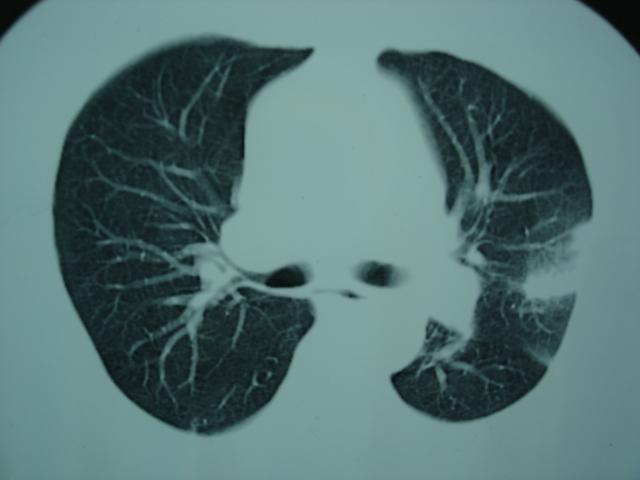

2009.6.4 2009.6.7 2009.8.21

第二次ct2009.6.7 住院后ect未见异常,查痰(阴性)大量抗菌素抗炎一个月后病灶明显变小,7月5号出院后回家后口服抗菌素45天